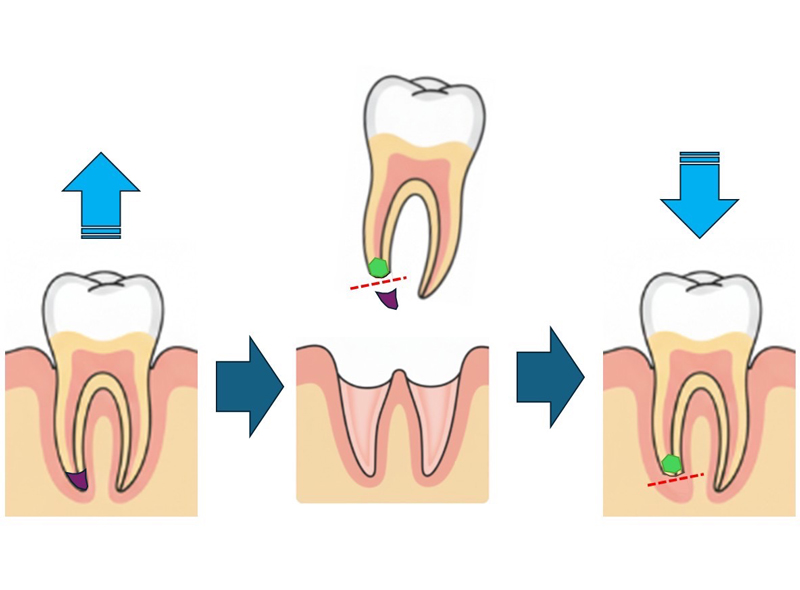

エクストリュージョン法

虫歯が深く、歯茎よりも上にあるべき歯質がほとんど残っていない状態の場合、基本的には抜歯の対象になってしまいます。

なぜなら、被せ物を装着するための土台作りは、歯茎よりも上に歯が出ている部分がないと作成できないからです。

そこで、歯茎に埋もれた歯を特別な方法で引き上げて露呈させ、人工歯を装着できるようにする治療法が「エクストリュージョン」です。

歯茎に埋もれた歯の根っこの中央部分にフックを装着し、真上からゴムやバネの力で引っ張り上げます。これにより埋もれていた根っこの上部が露呈するため、土台を作成することができるようになり、歯を抜かずに治療することが可能になるという仕組みです。

エクストリュージョンの流れ

Flow01

検査・型取り

適応できるか検査を行います。

どれくらい歯の根っこが残っているか、支える顎の骨の健康状態、固定する隣在歯の耐久性などをレントゲンなどで検査していきます。 -

Flow02

装置セット・ゴム交換

装置が完成したら、牽引する対象歯にフックを、隣在歯には固定用のワイヤーを取り付けていきます。ワイヤーとフックを歯科用ゴムでつなぐことで、歯を引き上げるための力が加わるようにします。装置をセットした後は徐々に牽引力を加えるため、約1週間に一度のペースでゴムの交換を行い、約1か月間、歯を持続的に引っ張ります。

Flow03

被せ物のセット

エキストリュージョンが完了したら周辺歯肉の整形を行います。整形した歯肉が落ち着いたのち、残っている歯と硬さが近似したグラスファイバー製の土台を立て、歯が折れにくい状態にして、プロヴィジョナルレストレーション(最終的な被せ物を見据えた仮歯)にて1か月確認を行ったのちに最終的な被せ物を作成します。